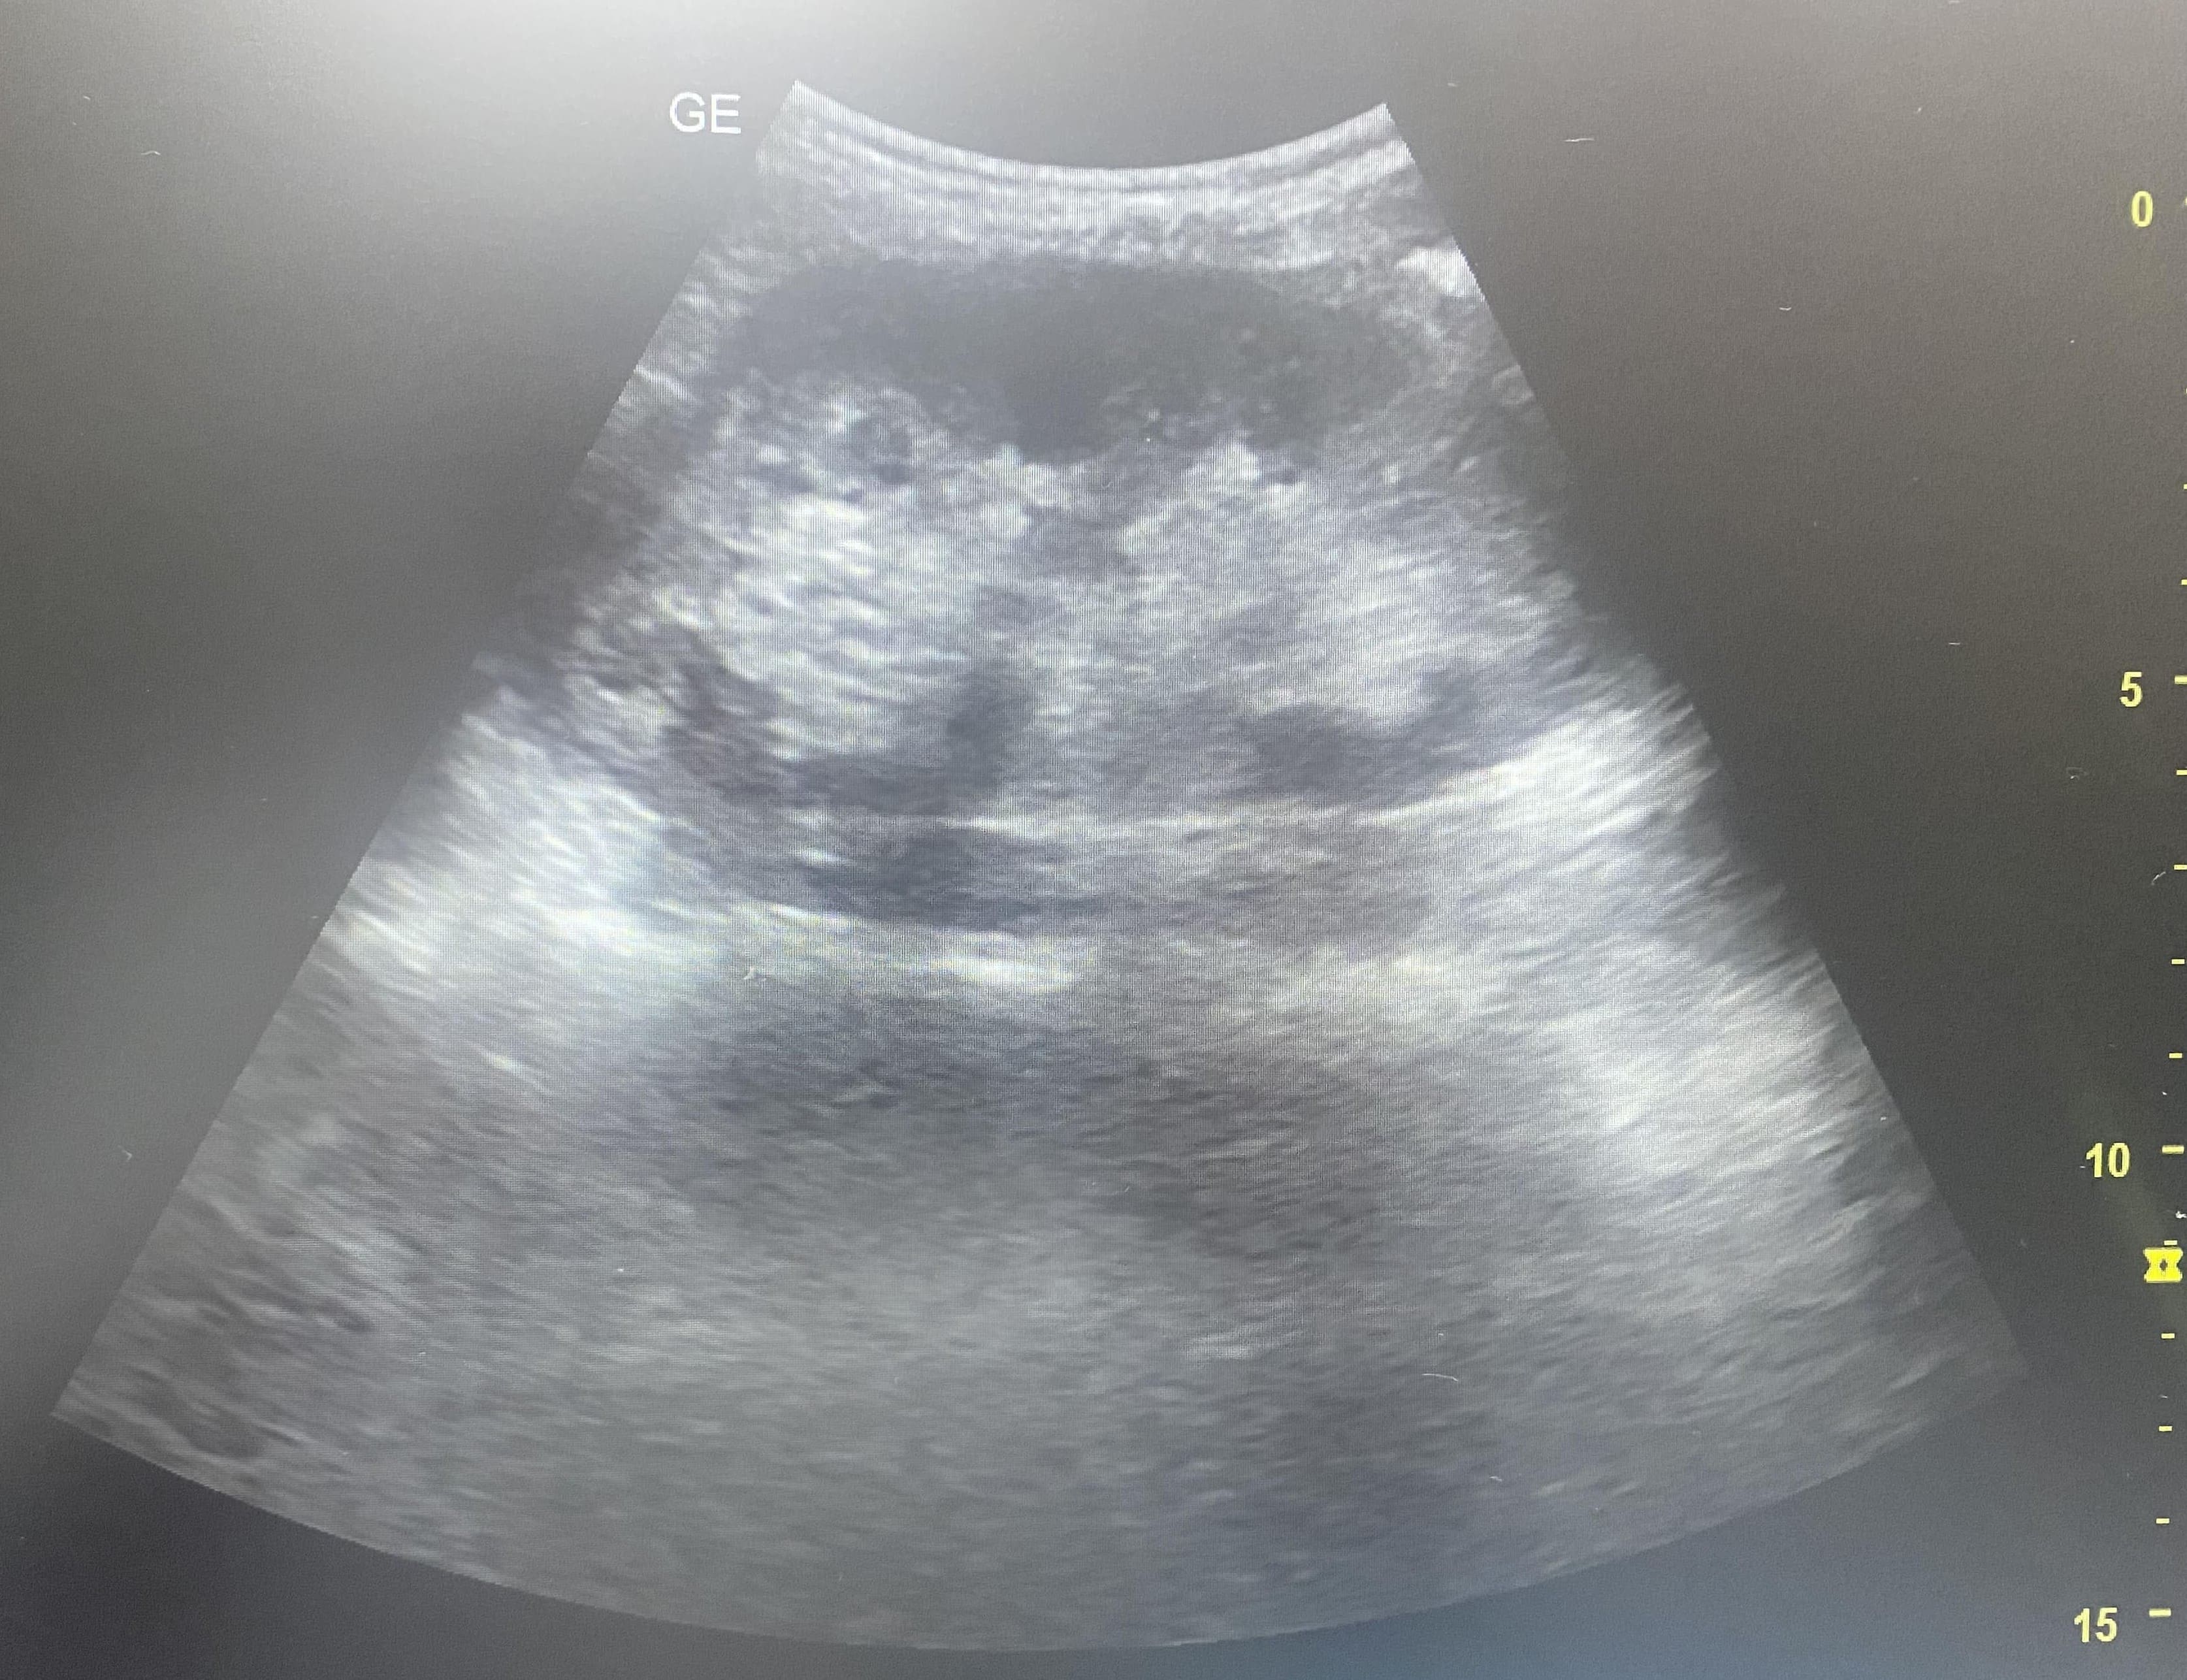

Vemos contenido anecogénico poco limpio bajo cúpulas diafragmáticas sobre todo en ambos flancos. Hígado con vasos portales muy birrefringentes. Riñón izquierdo algo desestructurado pero con difícil ventana.

La paciente ingresa en observación para tratamiento analgésico y preparación para cirugía urgente. En la analítica no presentaba leucocitosis pero sí reactantes de fase aguda elevados. Previa a la cirugía se realiza TAC abdominal con objeto de localizar la posible perforación que aparecía en antro gástrico y en la cirugía se objetiva el líquido ascítico purulento compatible con las imágenes captadas en ecografía.